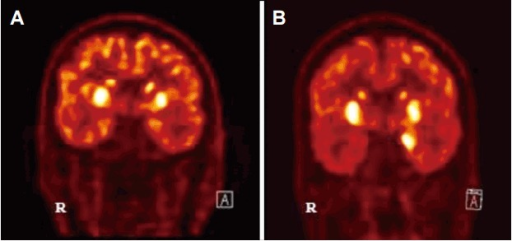

PMC5206099 er-6-2-45f9.png

Diagnosis of Autoimmune Encephalitis- a) basal ganglia hypermetabolism b) medial temporal hypermetabolsim